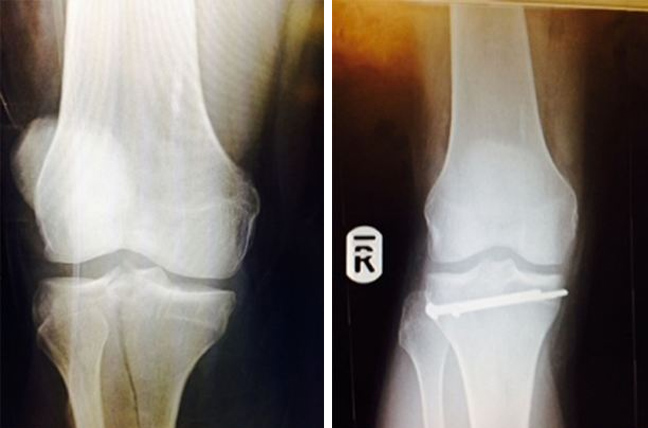

Η ζημιά που υπέστη ο Γουίλσον, όταν έσπασε το πόδι του.